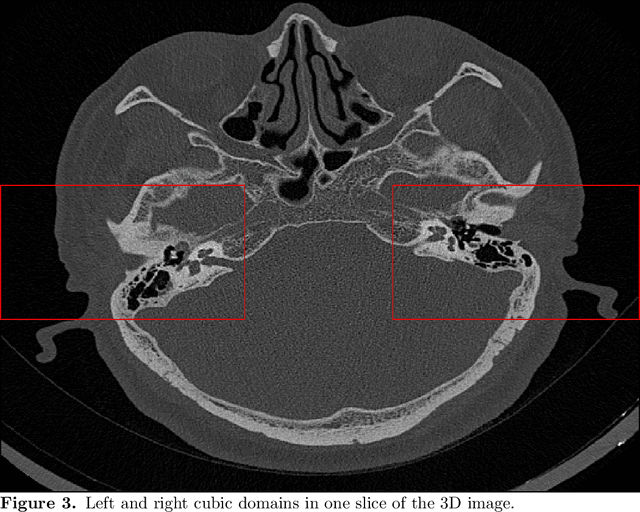

Abstract:The auditory ossicles that are located in the middle ear are the smallest bones in the human body. Their damage will result in hearing loss. It is therefore important to be able to automatically diagnose ossicles' diseases based on Computed Tomography (CT) 3D imaging. However CT images usually include the whole head area, which is much larger than the bones of interest, thus the localization of the ossicles, followed by segmentation, both play a significant role in automatic diagnosis. The commonly employed local segmentation methods require manually selected initial points, which is a highly time consuming process. We therefore propose a completely automatic method to locate the ossicles which requires neither templates, nor manual labels. It relies solely on the connective properties of the auditory ossicles themselves, and their relationship with the surrounding tissue fluid. For the segmentation task, we define a novel energy function and obtain the shape of the ossicles from the 3D CT image by minimizing this new energy. Compared to the state-of-the-art methods which usually use the gradient operator and some normalization terms, we propose to add a Ricci curvature term to the commonly employed energy function. We compare our proposed method with the state-of-the-art methods and show that the performance of discrete Forman-Ricci curvature is superior to the others.